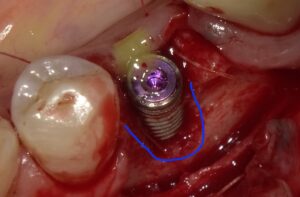

抜歯後インプラントを埋入しましたが骨が足りずネジが

見えています。

人工骨を填入しメンブレンを敷いたところです。